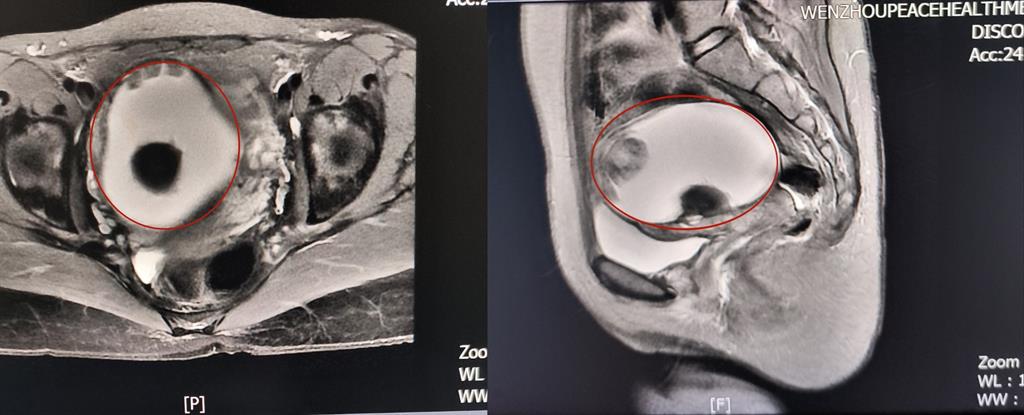

卵巢腫瘤?為進一步明確診斷,A女士在方主任建議下做了增強磁共振,影像結果提示:盆腔右側團塊狀占位伴多發(fā)成熟脂肪成分大小約89*100*71mm,考慮畸胎瘤可能性大。謎團逐漸解開,原來那個“怪胎”可能是畸胎瘤在作祟。